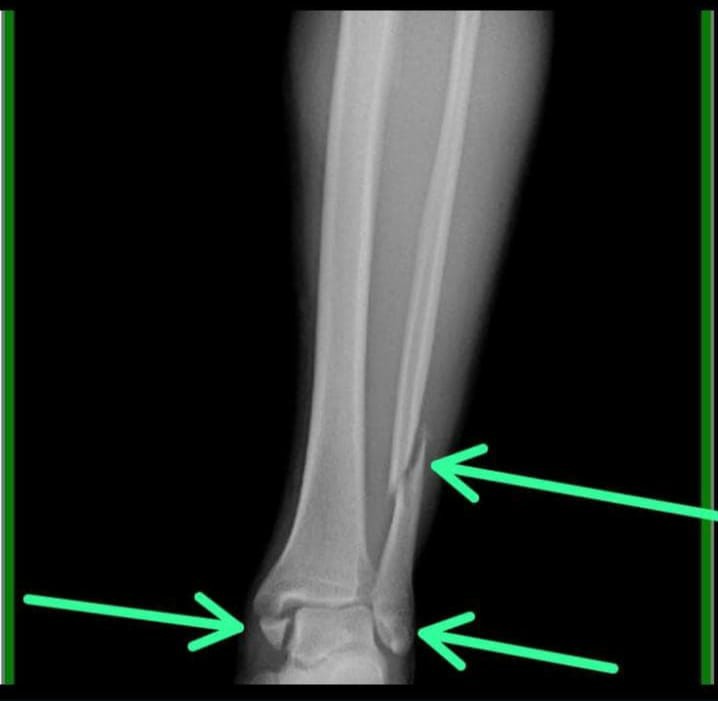

El 20 de diciembre, en el marco de una competencia que se desarrollaba en El Mangrullo, en Salto de las Rosas, Alejandro cayó de su equino y se produjo este daño en una de sus piernas. “Como dice mi hijo, ‘son riesgos que se corren’, y ha tenido otros golpes, otras cosas, pero esta vez se dio la mala suerte de que el caballo cayó sobre su pierna y el estribo le quebró la tibia y el peroné”, lamentó Patricia. Por su parte, el jinete recordó que si bien en el momento no sintió un gran dolor, al pararse se sintió raro. “Lo traté de mover, moví el tobillo pero lo sentía raro. Entonces a un compañero de la agrupación le pedí que me sacara la bota de montar, y al tocarme a la altura del tobillo sentí que algo se movía. Me di cuenta entonces de que había un problema grave”, exhibió.

El hombre está enyesado a la espera de ser operado, pues le tendrán que colocar una prótesis. “Si bien él tiene mutual esto lleva su tiempo, no le cubre toda la cirugía, le pagan una parte y otra hay que pagarla en efectivo, está sin trabajar y ese es el problema más grande: en este estado no puede trabajar”, señaló también.